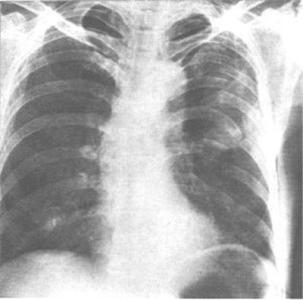

胸廓由胸骨、12对肋骨、12个胸椎相互连接共同构成。在胸廓骨折中肋骨骨折最为常见,约为90%。第4~7肋骨长而薄,最易折断。但如果造成第1~3肋或第11~12肋骨折,则往往外力打击很大,应密切注意有无合并胸内或腹内器官损伤。由于致伤暴力不同,可以产生单根或多根肋骨骨折,每根肋骨又可在一处或多处骨折。

胸廓由胸骨、12对肋骨、12个胸椎相互连接共同构成。在胸廓骨折中肋骨骨折最为常见,约为90%。第4~7肋骨长而薄,最易折断。但如果造成第1~3肋或第11~12肋骨折,则往往外力打击很大,应密切注意有无合并胸内或腹内器官损伤。由于致伤暴力不同,可以产生单根或多根肋骨骨折,每根肋骨又可在一处或多处骨折;单处骨折如无胸内脏器损伤,多不严重。但有几根相邻的肋骨同时两处以上骨折,可造成连枷胸。

1、局部疼痛,并于深呼吸、咳嗽、喷嚏时加重是肋骨骨折的主要症状。骨折断端刺破肺组织时可产生小量咯血。单根单处肋骨骨折,一般无明显呼吸困难和紫绀。当伴肺裂伤,支气管断裂、支气管阻塞合并肺不张时,可出现程度不等的呼吸困难。

2、如果伤后1~2d呼吸困难和紫绀逐渐加重,要警惕创伤后急性呼吸功能衰竭的发生。体格检查时,肋骨骨折局部有肿张、压痛,甚至触及骨擦感,用手挤压前后胸部能引起局部疼痛加重和骨擦感,此为肋骨骨折的特征,可以此与软组织损伤鉴别。多根多处肋骨骨折的病人,骨折区胸部扁平,失去正常弓形,并可有反常呼吸运动。但部分病人,因伤后疼痛处于保护性浅呼吸状态,反常呼吸运动可不明显。

3、肋骨断端刺破胸膜和肺,胸膜腔内气体经胸膜裂口进入胸部皮下组织,造成皮下气肿,或伴血胸、气胸时则有相应体征。病人因胸部疼痛而不敢深呼吸,所以伤侧呼吸音较低。由于深呼吸和咳痰受限,支气管内分泌物潴留,产生肺不张,此时患侧呼吸音明显减弱或消失。